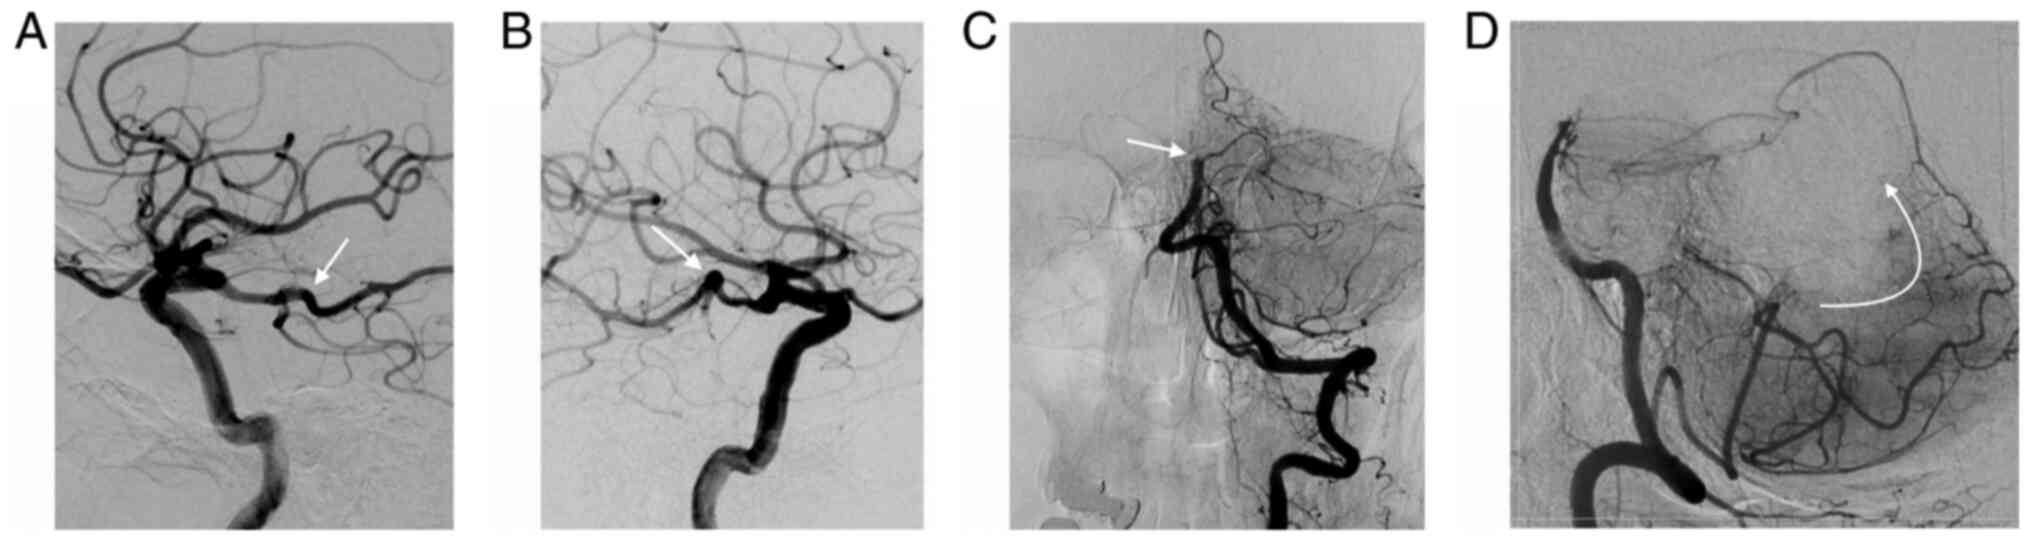

6. Posterior Circulation CT Angiography (pc-CTA) score

Figure 3

(A and B) Digital subtraction angiograms from bilateral internal carotid artery contrast injection show both posterior communicating arteries with a fetal configuration (white arrow) in a patient with basilar artery occlusion. (C and D) Contrast injection in the left vertebral artery reveal the distal basilar occlusion (white arrow) and collateral reconstitution of the superior cerebellar arteries through the posterior inferior cerebellar artery (curved arrow).

In their retrospective series of 15 patients, the primary endpoint was the correlation between the score and patient outcome at 3 months, as assessed by the modified Rankin Scale (mRS). A pc-CTA score <3 was associated with a good outcome (mRS ≤3) in all patients. In contrast, the contrary, if the score was ≥3, patient outcome was worse (28). In a retrospective study performed by Alemseged et al (29) a pc-CTA ≥3 predicted a poor outcome if adjusted for age (OR, 1.6; 95% CI, 1.1-2.1; P=0.008), but not for NIHSS.

7. Posterior Circulation Collateral Score (pc-CS)

The investigators enrolled in the Basilar Artery International Cooperation Study (BASICS) developed this CT angiography score [Posterior Circulation Collateral Score (pc-CS)] as a prognostic tool for identifying patients who present with a poor outcome (30). The score allots 1 point for each patent posterior inferior cerebellar artery (PICA), anterior-inferior cerebellar artery (AICA), superior cerebellar artery (SCA) and posterior communicating artery (Pcom) if its diameter is smaller than the ipsilateral PCA, or 2 points if it has a diameter equal to, or larger than the ipsilateral PCA. A score of 10 implies that all the aforementioned branches are patent, while a score of 0, means that all of them are not visible/occluded. Three intervals of severity were defined for the pc-CS: Poor 0-3, intermediate 4-5, and good 6-10. Patients with a poor score had higher median NIHSS at admission and had more frequently severe symptoms (tetraplegia, locked-in state or coma), than patients with an intermediate or a good score. Moreover, there was a 25% lower risk of poor outcome in patients with a good pc-CS score, compared to those with a poor score, after adjustment for age, time to treatment and treatment modality (RR, 0.74; 95% CI, 0.58-0.96). There was no significant difference between poor outcome compared to intermediate outcome. An important finding of their analysis was the crucial role played by the presence or absence of PComs, or their diameter. A poor outcome is more frequently encountered if one or both PComs are absent, and if their diameter is small (30).

Ravindren et al further emphasized the crucial importance of the PComs in BAO, by analyzing the presence or absence of collaterals, represented by the PCom and PICA-AICA anastomosis. Patients with collaterals had an almost 3-times higher likelihood of a good outcome at 3 months (OR, 2.73; 95% CI, 1.01-7.39), while absence of both PComs was associated with a 60% decreased chance of good functional outcome at 90 days (OR, 0.39; 95% CI, 0.17-0.93). Furthermore, even unilateral absence of a PCom led to a 2-fold increase in mortality (OR, 2.17; 95% CI, 1.14-4.13) (25).

When time-to-treatment ≤6 or >6 h and revascularization status were taken into account, all patients with a favorable pc-CS had a good outcome (OR, 9.4; 95% CI, 1.4-64; P=0.02). Conversely, an unfavorable pc-CS was associated with good outcome only in patients treated within 6 h from symptom onset, and not beyond (OR, 5.5; 95% CI, 1.4-2; P=0.01) (31).

8. Basilar Artery on Computed Tomography Angiography (BATMAN) Prognostic Score

BATMAN is a 10-point score that incorporates thrombus burden and extent of primary collaterals. It allocates 1 point for the patency of either the vertebral artery, proximal BA segment, middle BA, distal BA, for each PCA and 2 points for each PCom larger than 1 mm in diameter. If smaller, i.e. hypoplastic, 1 point is given to each. If a fetal PCom is present, it receives 3 points (29). The optimal cut-off value to discriminate between good and bad functional outcome is a score of 7. A BATMAN score <7 is an independent predictor of poor outcome (OR, 6.9; 95% CI, 1.4-33; P=0.01) and an increased risk of mortality (OR, 7.4; 95% CI, 1.2-44; P=0.03) after adjustment for age and NIHSS. The score did not influence recanalization success between the two groups. If recanalization was not achieved, the rates of poor outcome were similar. However, if recanalization was successful, only 24% of the patients had a poor outcome if BATMAN was ≥7, compared to 76% if <7. Compared to the prognostic scores reviewed earlier, BATMAN performed better than pc-CS in terms of accuracy and interrater agreement, but not better than pc-CTA (29).

In a recent paper, Alemseged et al (31) assessed the prognostic value of BATMAN correlated with time-to-treatment (TTT) and recanalization status (mTICI). In patients with a favorable score treated within or even beyond 6 h, complete revascularization (mTICI 2b-3) was associated with a good outcome (adjusted OR, 15.8; 95% CI, 1.4-175; P=0.02). However, in cases with an unfavorable score, revascularization was associated with good outcome only if obtained within 6 h (OR, 15; 95% CI, 1.9-124; P=0.01); findings that support the relevance of collaterals and thrombus load in late time-windows for BAO.